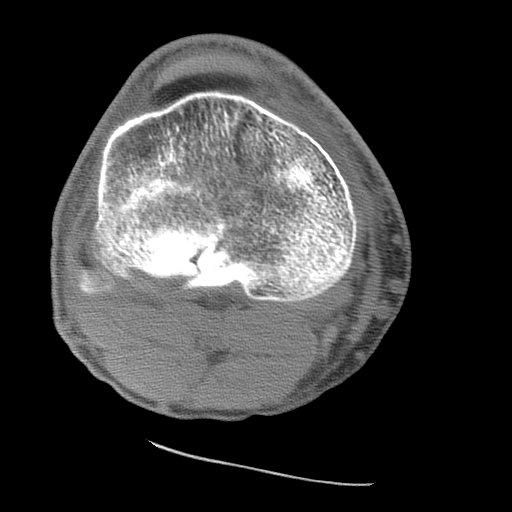

Axial CT depicts the fracture involving the posterior aspect of the lateral tibial plateau, the source of the bone marrow producing the lipohemarthrosis.